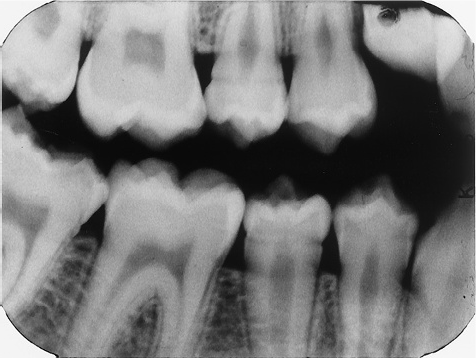

The radiograph shows evidence of

2 / 30